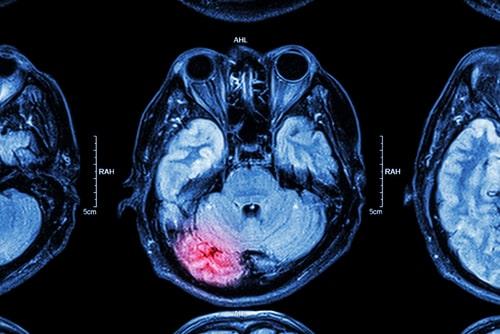

When is a Head Injury Considered Catastrophic?

Head injuries can range from fairly minor to catastrophic. Some types of head injuries sustained in accidents can be life-altering. Traumatic brain injuries may impact a person’s cognitive or physical ability for the rest of her life. Some people who have suffered these injuries will require permanent round-the-clock care in a skilled nursing facility or from a home health aid. Others will never be able to return to their careers or finish school. Less serious head injuries might be serious but not catastrophic. If you sustained any type of head injury due to an accident caused by another party’s negligence, you should consult a Greenwich, CT catastrophic injuries lawyer immediately. You may be entitled to significant compensation.

Head injuries can range from fairly minor to catastrophic. Some types of head injuries sustained in accidents can be life-altering. Traumatic brain injuries may impact a person’s cognitive or physical ability for the rest of her life. Some people who have suffered these injuries will require permanent round-the-clock care in a skilled nursing facility or from a home health aid. Others will never be able to return to their careers or finish school. Less serious head injuries might be serious but not catastrophic. If you sustained any type of head injury due to an accident caused by another party’s negligence, you should consult a Greenwich, CT catastrophic injuries lawyer immediately. You may be entitled to significant compensation.

Head Injuries That Cause Permanent Disability Are Catastrophic

If a brain injury permanently impacts the types of activities you can and cannot do or changes your career prospects, your injury is likely considered catastrophic. You do not need to be totally disabled and unable to work entirely for your traumatic brain injury to be treated as a catastrophic injury. For example, say you were working as a history teacher, but your brain injury interfered with your long-term memory to the point where you can no longer remember enough information about the subject matter you teach to write a lesson plan without re-learning the material yourself. In that case, you probably have a catastrophic injury.